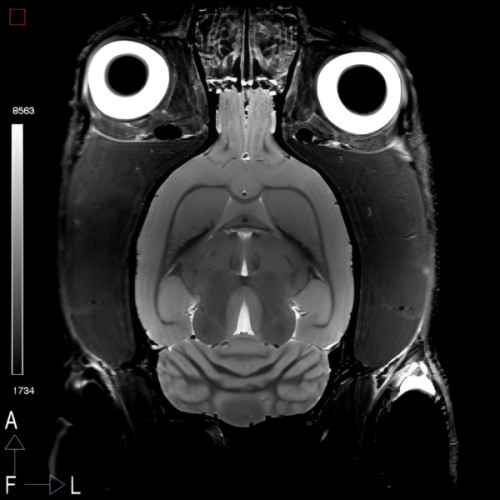

El cerebro es uno de los órganos más complejos del cuerpo humano. Las técnicas de imagen, como la tomografía computarizada, resonancia magnética o la imagen nuclear, nos permiten estudiar la anatomía y la función correcta del cerebro. Esta actividad pretende acercar a los asistentes al apasionante mundo de la imagen biomédica. Ponente: María Luisa Soto Montenegro.